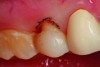

Fig 4. After apical repositioning of the gingival margin over tooth No. 4 with a diode laser, the overcontouring of the porcelain to accommodate the preoperative gingival position is evident. The excessive emergence profile on the disto-proximal aspect of the veneer restoration has caused a chronic marginal periodontitis in the area so that bleeding is always present regardless of the level of home care.

Figure 4

Figure 1 and Figure 2 show full-smile and intraoral full-arch views of the patient’s preoperative condition. The retracted full-smile image revealed disparate gingival heights over teeth Nos. 8 and 9. The proximal-facial line angles, particularly of the maxillary central incisors, were indistinct and rounded, contributing to a more “square” silhouette of the facial outline form. The maxillary anterior teeth appeared much larger in the cervico-incisal dimension with a dramatic decrease in height starting in the first premolar area (Figure 3). Esthetic harmony cannot always be achieved without addressing both hard and soft tissues and unfortunately, some clinicians “only see the white and not the pink.” The decreased height of the posterior teeth helped to contribute to the problem of the anterior teeth appearing too large. Prior to tooth preparation, a soft tissue correction was made with a diode laser (Picasso Diode Laser, AMD Lasers, amdlasers.com), which made the bulbous emergence profile of the existing veneer painfully evident. Because the patient had no second premolar due to extraction and orthodontics performed when the patient was younger, symmetry of the positions of the gingival margins was very important to the overall esthetics of the case. An imaginary line was drawn from the cervical height of contour of the maxillary cuspid to the gingival margin above the mesio-buccal root of the maxillary first molar. The gingival margin of the maxillary premolar needed to be on this line. If biologic width was violated, bony crown lengthening would be required (Figure 4). In this case, a closed-flap crown lengthening was performed with an ErCr: YSGG all-tissue laser (iLase® Plus, Biolase Technologies, biolase.com) to reestablish the proper 3-mm distance from the free gingival margin to the crest of bone. When healed, the new restoration would appear longer in the cervico-incisal dimension and gingival harmony would be achieved.